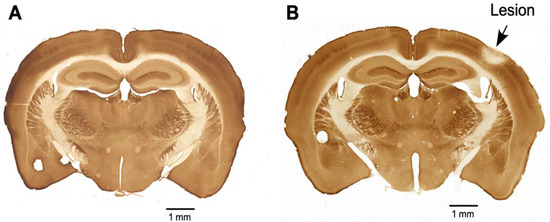

2.4. Cytochrome Oxidase Reaction

The four animals with sham control and the four animals with PTL were given saline for seven days post-lesion. On the eighth day, the animals were perfused transcardially with PBS (NaCl (80 gm), KCl (2 gm), Na2HPO4 (11.4 gm), and KH2PO4 (23.2 g) in 900 mL of water and then forming a volume of 1 L, pH-7.4) to clear the blood and then with 4% paraformaldehyde in PBS (PFA) to fix the tissues. The brains were removed and postfixed for 24 h in 10% sucrose in a PFA solution at 4 °C. The brains were cryoprotected by sequentially allowing them to sink in 20% sucrose in PBS, followed by 30% sucrose in PBS at 4 °C. The forebrain was cut into 30 µm thick sections on a sliding microtome. Every sixth section was reactive for cytochrome oxidase. The sections were washed three times with PBS at room temperature and then immersed in freshly prepared cytochrome oxidase staining solution (in 30 mL of 0.1 M phosphate buffer, sucrose (5 g), cytochrome C (Sigma, St. Louis, MO, USA; 25 mg), and DAB (Sigma; 20 mg) were dissolved, and the volume of solution was made up to 50 mL with phosphate buffer). The sections were incubated for 5 h at 37 °C. The sections were then washed twice with PBS, mounted on gelatin-coated glass slides, air dried, and coverslipped with DPX mounting medium. The sections were observed under a light microscope and imaged. Figure 1 shows sections from the brains of sham control animals (Figure 1A) and PTL animals (Figure 1B). In Figure 1B, the cortical region where the photothrombotic lesion was done appears pale, suggesting that cells in the area are dead, as indicated by the absence of cytochrome oxidase activity.

Figure 1.

Photomicrograph showing brain sections that were reacted for cytochrome oxidase from (A) a sham control mouse and (B) a PTL mouse. The lesioned area, indicated by the arrow, shows a region with inactive cells.